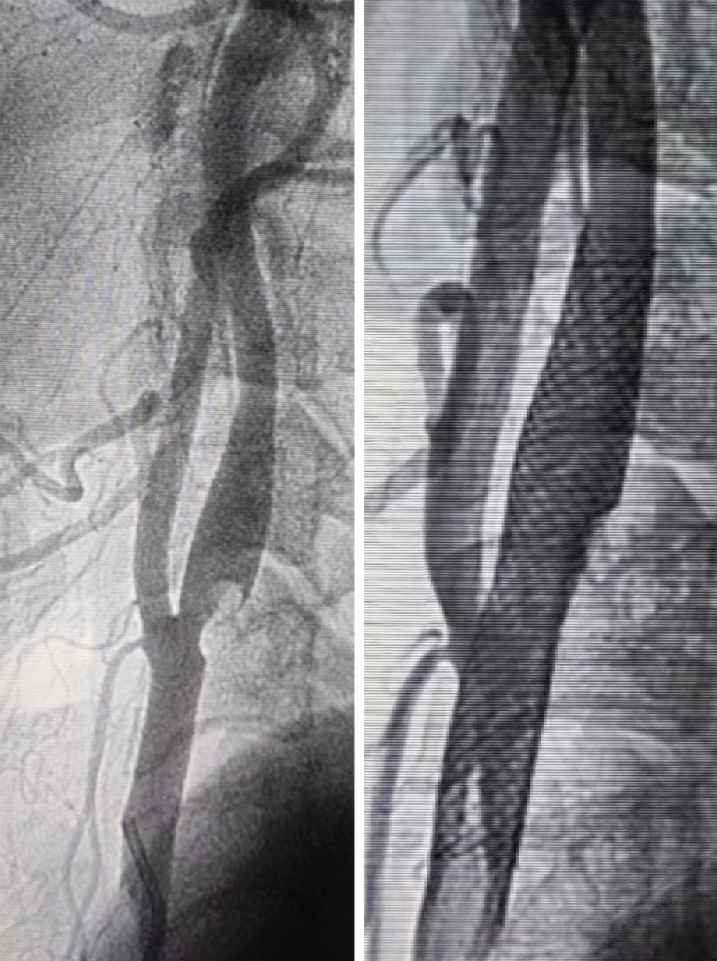

DSA示:牛角弓,左侧颈内动脉起始部狭窄

• 患者左侧颈动脉狭窄,狭窄程度>50%,合并既往左侧颞叶梗塞,具备明确手术指征;患者拒绝行颈动脉CEA手术,要求选择CAS术;患者主动脉弓形为牛角弓,经股建立通路较繁琐,适于经桡建立左侧颈动脉通路;

什么叫桡鞘Epath®长鞘经桡入路丨冯军教授团队:Epath®长鞘经桡入路行颈动脉狭窄CAS术一例_https://www.jmylbn.com_新闻资讯_第9张

排空球囊后造影示狭窄改善明显,撤出球囊后交换7*40mm Wallstent支架至病变部位打开。

造影示支架打开良好,贴壁良好,病变节段覆盖完全,回收保护伞,再次造影示远端终末血管无栓塞,撤除治疗系统,手术结束。